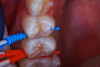

(6.) After exposure of disto-occlusal caries, SDF is applied, followed by a coating of fluoride varnish.

Figure 6

(7.) After exposure of disto-occlusal caries, SDF is applied, followed by a coating of fluoride varnish.

Figure 7

(8.) After exposure of disto-occlusal caries, SDF is applied, followed by a coating of fluoride varnish.

Figure 8